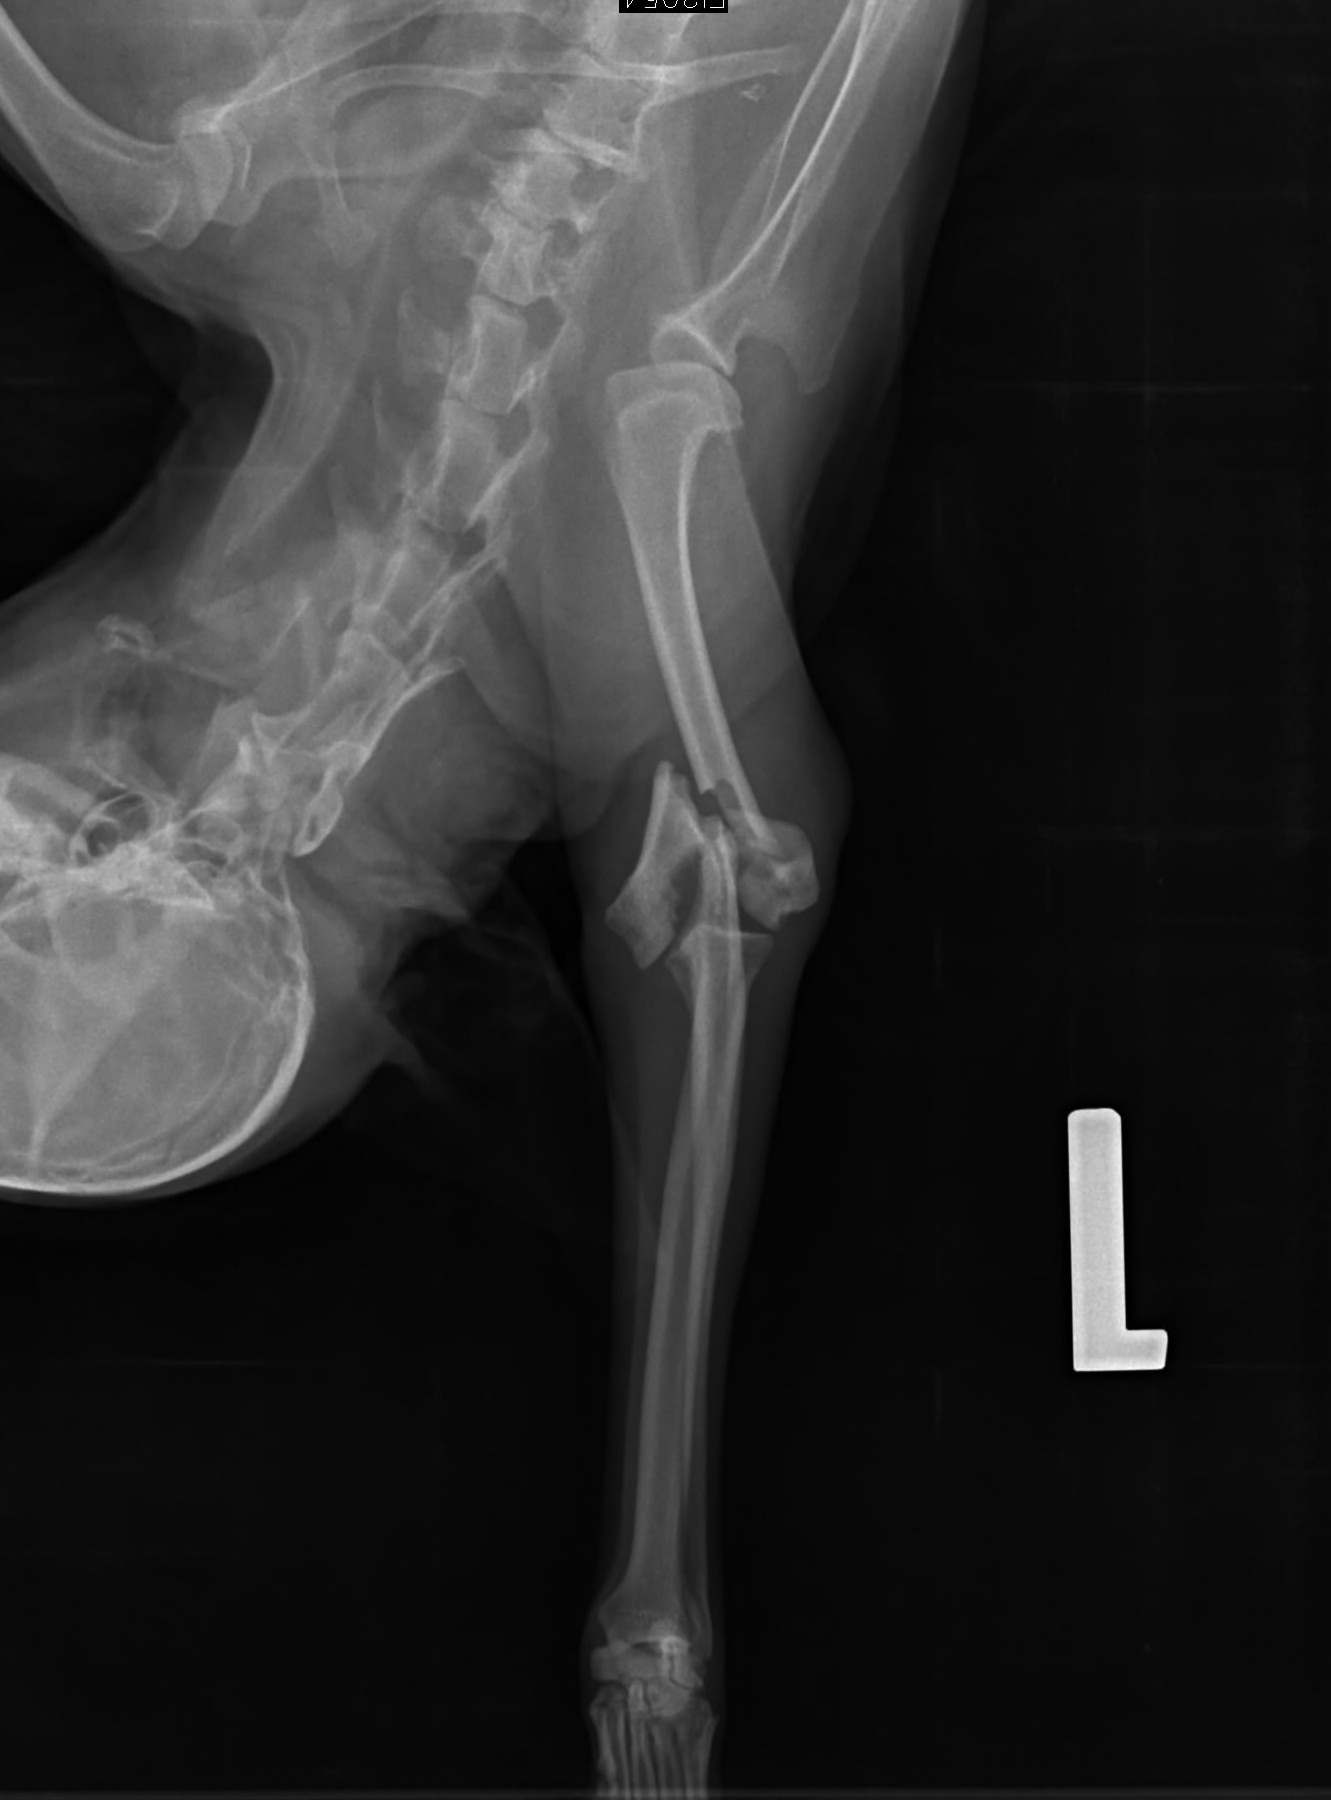

Właściciel od samego początku jasno powiedział, że nie dołoży ani złotówki do leczenia. Gdy usłyszał diagnozę — skomplikowane złamanie łapy, złamanie miednicy i liczne obrażenia — zażądał uśpienia psa.

W sobotę natychmiast zawieźliśmy Dżakusia do kliniki w Bohuminie. Otrzymał tam fachową pomoc, pełną diagnostykę, kroplówki i całodobową opiekę szpitalną. Niestety jego stan był znacznie gorszy, niż przypuszczaliśmy.

Dodatkowo wykryto anaplazmozę, poważne problemy z krwią oraz dramatycznie złe wyniki morfologii i biochemii. Aby mógł zostać zoperowany, konieczna była pilna transfuzja krwi. Po krew musieliśmy jechać aż do Katowic. Koszt samej krwi wyniósł 900 zł.

Przed Dżakusiem kilka operacji. Każda trudna, długa i bardzo obciążająca dla jego wyniszczonego ciała. Leczenie prowadzone jest etapami tylko po to, by miał szansę to wszystko przeżyć.